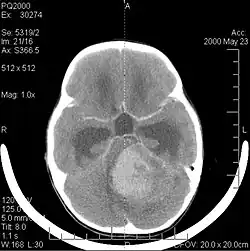

La tomodensitométrie (TDM) et L'imagerie par résonance magnétique (IRM) peuvent détecter efficacement une néoplasie dans le cerveau. L'IRM est plus sensible que la TDM pour identifier les lésions, mais présente des contre- indications pour les patients porteurs de stimulateurs cardiaques, de prothèses incompatibles, de clips métalliques et contre-indications. La TDM reste la méthode de choix pour détecter les calcifications au sein des lésions ou les érosions osseuses de la calotte ou de base du crâne. L'utilisation d' agents de contraste, iodés dans le cas du scanner et paramagnétiques (gadolinium) dans le cas de l'IRM, permet l'acquisition d'informations sur la vascularisation et l'intégrité de la barrière hémato-encéphalique, une meilleure définition de la tumeur tumorale par rapport à l' œdème environnant et à la génération d' hypothèses sur le degré de malignité. L'examen radiologique permet également d'évaluer les effets mécaniques et les modifications importantes des structures cérébrales résultant de la tumeur, telles que l' hydrocéphalie et les hernies, dont les effets peuvent être fatals. Enfin, en préparation à la chirurgie, ce diagnostic peut être utilisé pour déterminer la localisation de la lésion ou l'infiltration de la tumeur dans des zones vitales du cerveau. À cette fin, l'IRM est plus efficace que la tomodensitométrie car elle peut fournir des images en trois dimensions.

Les outils d'imagerie radiologique diagnostique mettent en évidence la modification du tissu néoplasique par rapport au parenchyme cérébral normal (par le biais de modifications de la densité tissulaire imagée électroniquement en TDM et de l'intensité du signal en IRM). Comme la plupart des tissus pathologiques, les tumeurs sont également reconnaissables par une accumulation accrue d'eau intracellulaire. Dans la tomodensitométrie, ils apparaissent hypodenses, c'est-à-dire de moindre densité que le parenchyme cérébral, dans la tomographie par résonance magnétique nucléaire avec relaxation spin-réseau hypointense et en relaxation spin-spin ainsi que l' hypersignal en pondération protonique (PD).

La tomodensitométrie du cerveau montre généralement une masse tissulaire qui peut être améliorée par l'un ou l'autre contraste. Au scanner, les gliomes de bas grade apparaissent généralement isodenses au parenchyme normal et peuvent donc ne pas présenter de rehaussement de contraste. De même, les lésions de la fosse crânienne postérieure sont difficiles à identifier au scanner. Par conséquent, les seuls résultats d'une telle tomographie ne sont pas toujours suffisants à des fins diagnostiques. Dans les cas douteux, l'utilisation de l'imagerie par résonance magnétique plus sensible est indispensable.